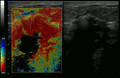

يُظهر التصوير الإلستوجرافي أنسجة سرطانية شديدة في التصوير بالموجات فوق الصوتية.

-

تظهر صورة الموجات فوق الصوتية كتلة غير منتظمة الشكل من سرطان الثدي.